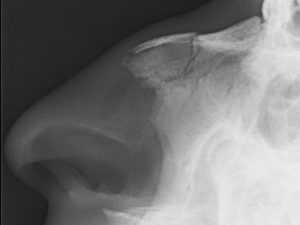

С данной травмой обращаются к врачу — отоларингологу. Врач осмотрит пациента, оценит степень травмы, соберет анамнез. При пальпации носовой области определит болезненный участок, наличие воздуха, крепитацию фрагментов кости и подвижность наружного носа. Также специалист выявит вид деформации носовой пирамиды и степень отека мягких тканей. Очень важно обратить внимание на наличие у пострадавшего кровотечения и головной боли, потери сознания, рвоты или тошноты. Обязательно проводят инструментальные исследования — рентген и риноскопию.

Рентгенографическое исследование поможет определить вид травмы (открытый, закрытый, со смещение или без) и локализацию повреждения (иногда это можно определит путем пальпации). Риноскопия выявляет степень отека слизистой оболочки, вероятное искривление перегородки, место разрыва слизистой и первоисточник носовой геморрагии. Важно определить наличие сопутствующих недугов и носовых повреждений в прошлом.

Рентгенографическое исследование черепа. Снимки, полученные в ходе обследования, позволяют врачу увидеть места перелома и количество, а также смещение отломков. Помимо травмы органа дыхания, с помощью рентгенографического исследования выявляются возможные повреждения черепных костей.

Рентген носа позволяет не только определить локализацию отломков и состояние костей травмированного органа, но и сопутствующие повреждения черепа. На рентгеновском снимке четко видны разрывы костной ткани и все линии перелома. Рентгенография осуществляется в двух проекциях для более полного поминания травмы.